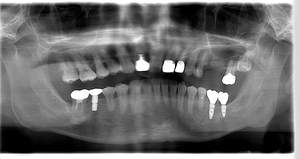

インプラント治療の症例4

レントゲン写真

- Befor

- After

口腔内写真

| 年齢 | 50代・男性 |

|---|---|

| 主訴 | 部位:左下6番7番 主訴:左下奥歯腫れて痛い。 |

| 治療内容 | 左下6番抜歯、左下6番7番骨造成、インプラント埋入 |

| 治療費 | 合計:1,232,000円 ・内訳 診断料:55,000円 サージカルガイド2本:66,000円 GBR:110,000円×2本 埋入料:165,000円×2本 静脈内鎮静麻酔:77,000円 2次OPE:22,000円×2本 仮歯:55,000円×2本 上部構造(フルジルコニア):165,000円×2本 (2023年1月現在) |

| 治療期間 | 約8ヶ月 |

| リスク・副作用 | リスク・副作用 |

| 治療方針 | 元々支台歯に負荷がかかりやすいとされている延長ブリッジを抜歯し、1本単体でしっかりかめるようにインプラントを2本埋入した。骨吸収も進んでいたため、※GBR法で骨造成を同時に行った。 治療と並行して、全顎的な歯周病治療も行い、今後は歯周病が進行しないよう、こまめにメンテナンスに通っていただく。 |

| 特記事項 | ※1 GBR・・・骨再生誘導法。骨の高さや厚みを人工骨や人工膜などを使用し再生する方法 |

| 担当者所見 | 6番は歯根分割された被せ物が7番の欠損部との延長ブリッジとされており、強い咬合と歯周病も相まって負荷がかかり動揺し、歯として機能しなくなったため、抜歯となった。 |